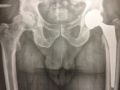

Chirurgie de la hanche à Angers prothèse totale de hancheProthèses totales - nombre de pose en 2018: 300 P.T.H.

Matériel - Tiges : titane, chrome cobalt, tiges courtes

Cotyle : sans ciment impacté, cimenté, double mobilité, céramique pré-embarquée

Couple de friction : Alumine-Alumine, chrome cobalt-polyéthylène